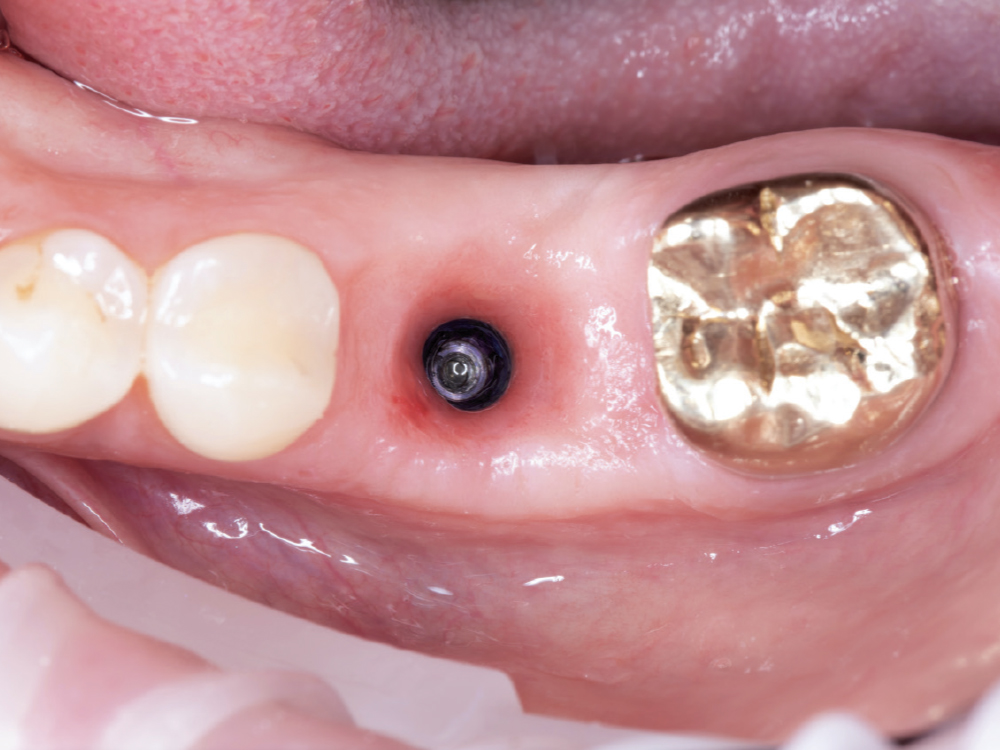

Implant post scan on left side of mouth

Implant post scan pointing down

Implant post scan close up

Verify the Scans Before Dismissing the Patient. Review all critical areas while the patient is still in the chair, ensuring complete scan body capture, accurate contacts, adequate tissue detail, and proper bite registration. Zoom in on critical areas to verify resolution and completeness. It takes only two minutes to verify a scan, but potentially days before a patient is able to return to your practice. Use the scanner’s analysis tools to identify distortions or artifacts.